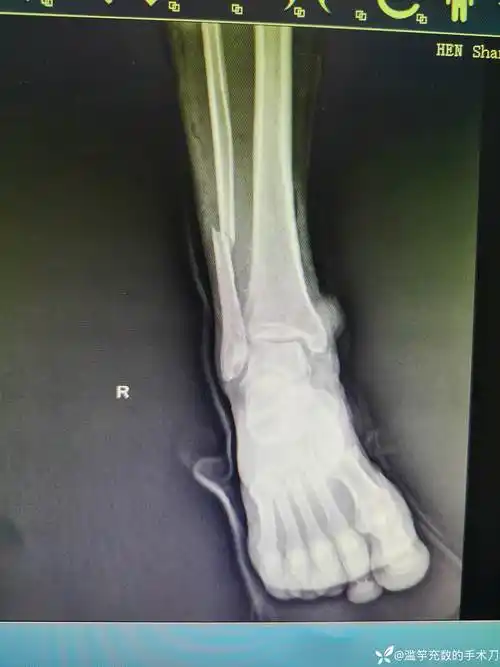

如此艰辛历程旋前外旋型踝关节骨折